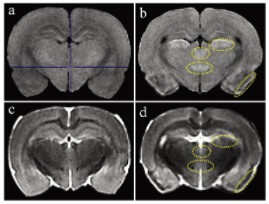

圖1顯示了T1和T2加權MRI圖像。與對照組相比, 匹羅卡品處理的動物在梨狀皮質、丘腦外側核、丘腦室周后核和大腦下丘腦后核的T1加權圖像顯示出高T1信號(圖1a和b)。在匹羅卡品處理的動物的T2加權圖像中,與對照組相比,在梨狀皮質觀察到低T2信號,對應于高T1信號區(圖1c和d)。其他3個高T1信號區的T2信號強度與對照組相當(中等強度)(圖1c和d)。

當前易于使用的緊湊型小動物磁共振成像系統在匹羅卡品誘導的大鼠腦損傷的臨床前毒理學病理檢查中的適用性。高T1和低T2信號顯示明顯的組織病理學神經元損傷,盡管組織病理學檢查更為敏感。